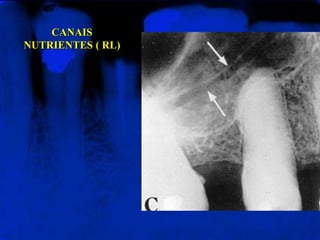

CANAIS NUTRENTES ( RL)

Vistos como linhas

radiolúcidas, que

correspondem aos trajetos

intra-ósseos das arteríolas ou

veias.

CANAIS

NUTRIENTES ( RL)

CANAIS NUTRENTES (RL) Vistos como linhas radiolúcidas, que correspondem aos trajetos intra-ósseos das arteríolas ou veias.